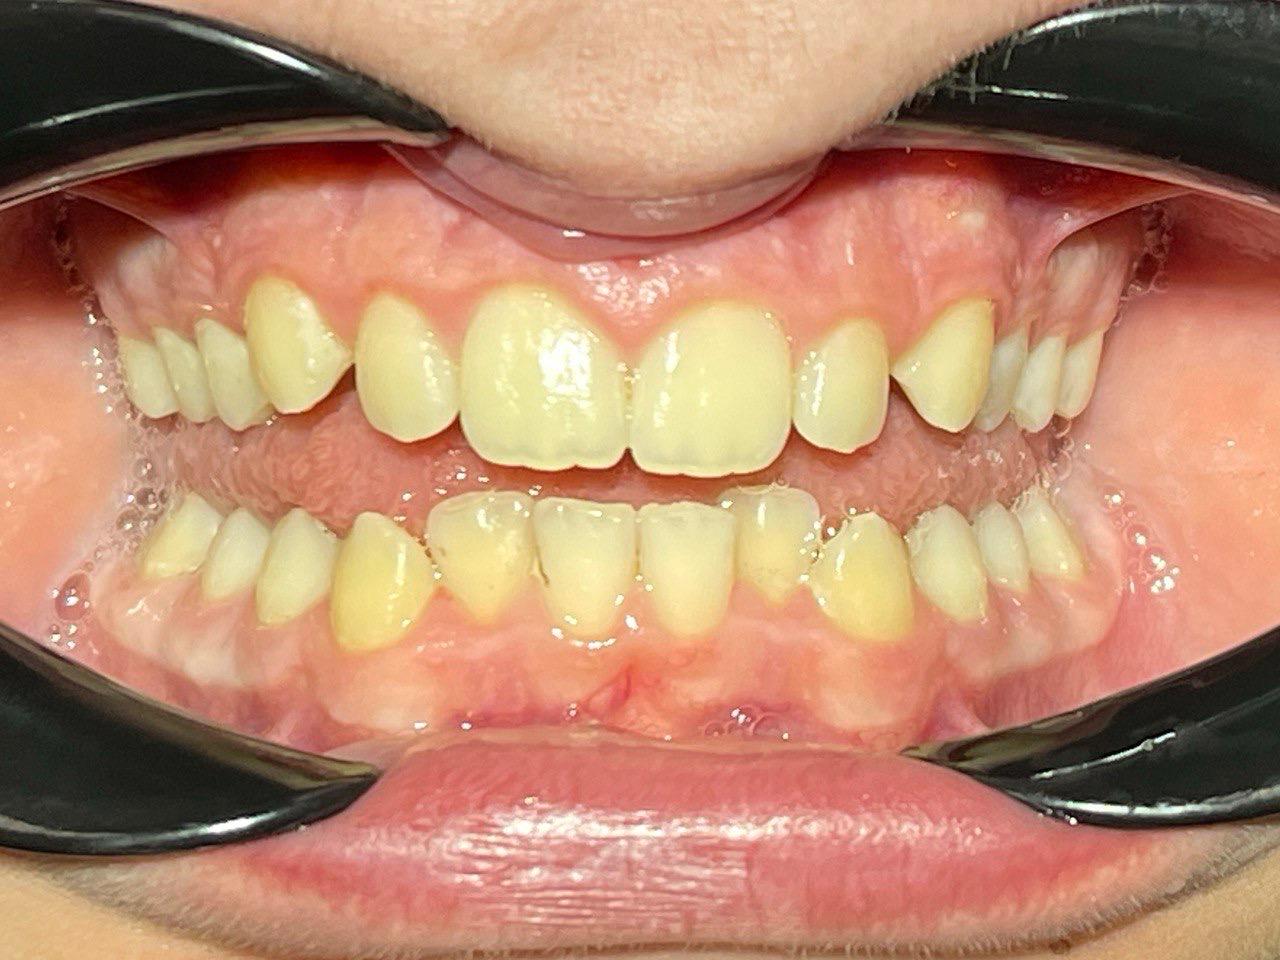

Выявленные проблемы

• Мезиальная окклюзия

• Периодонтит зуба 4.6.

• Дистализация нижнего зубного ряда с опорой на ортовинт

Брекет-система Q